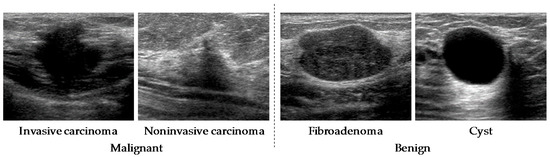

2.1. Materials